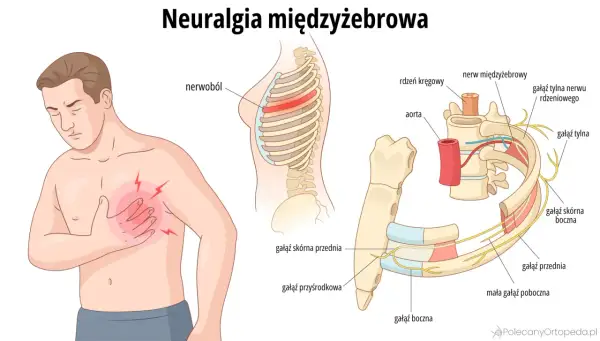

Wędrujące nerwobóle - Jak je rozpoznać i skutecznie leczyć?

Wędrujące nerwobóle? Odkryj przyczyny, diagnostykę i skuteczne leczenie bólu, który zmienia miejsce. Sprawdź, kiedy działa rehabilitacja!